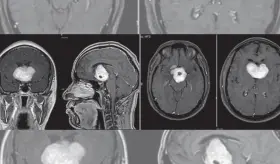

Actualmente hay tratamientos de inmunoterapia los cuales inhiben la proteína BCL2, encargada de evitar que la célula maligna muera.